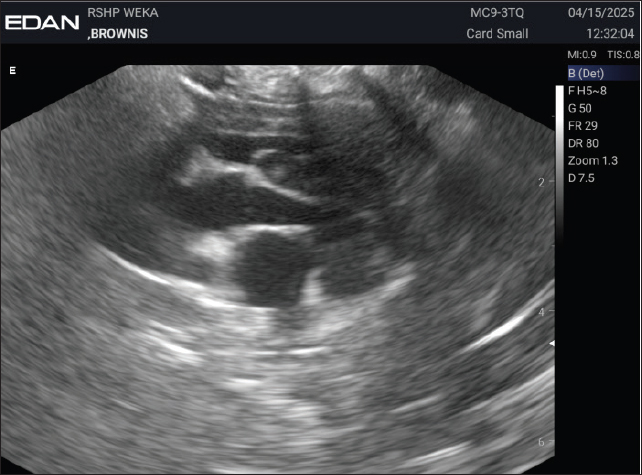

Figures 3 and 4 show the results of the echocardiographic examination, while Figure 5 presents the electrocardiographic findings of the dog, Brownis. The motion mode (M-mode) evaluation (Fig. 3) was used to measure the left ventricular dimensions during systole and diastole, as well as systolic and diastolic function values. The M-mode results showed a decrease in interventricular septal thickness during diastole and systole (IVSTd=5.28 mm, IVSTs=3.80 mm) and a reduction in left ventricular internal dimension during systole (LVIDs=8.66 mm). Figure 4 represents the brightness mode (B-mode) evaluation, used to assess valve thickening and movement. The results showed abnormal valve movement with normal valve structure. Figure 5 presents the electrocardiographic examination performed at a paper speed of 50 mm/second using a 5-lead system, which revealed sinus arrhythmia.

Fig. 4. Echocardiography B mode of Brownis.

In the case of brownies, electrocardiography (ECG) showed an irregular rhythm with the presence of P waves, QRS complexes, a 1:1 P wave to QRS complex ratio, T waves, and a heart rate of 111 bpm. B-mode echocardiography revealed abnormal valve movement with normal valve structure. M-mode measurements were as follows: IVSTd 3.80 mm (normal 5.2–6.5 mm), LVIDd 17.32 mm (normal 15.83–18.53 mm), EDV 8.80 ml, LVPWd 6.97 mm (normal 5.1–6.1 mm), IVSTs 5.28 mm (normal 6.95–8.22 mm), LVIDs 8.66 mm (normal 9.01–11.5 mm), ESV 1.39 ml, SV 7.41 ml, EF 84.20% (normal 25%–55%), FS 50% (normal 55%–85%), and LVPWs 6.55 mm (normal 6.6–8.12 mm) (Cerbu et al., 2023). Color Doppler examination demonstrated turbulence at the valve, indicating abnormal blood flow velocity, visualized as red and blue gradients on the Doppler image. NT-proBNP levels were within normal limits at 0.5 ng/ml, whereas cardiac troponin I was elevated at 0.13 ng/ml, indicating myocardial cell injury.